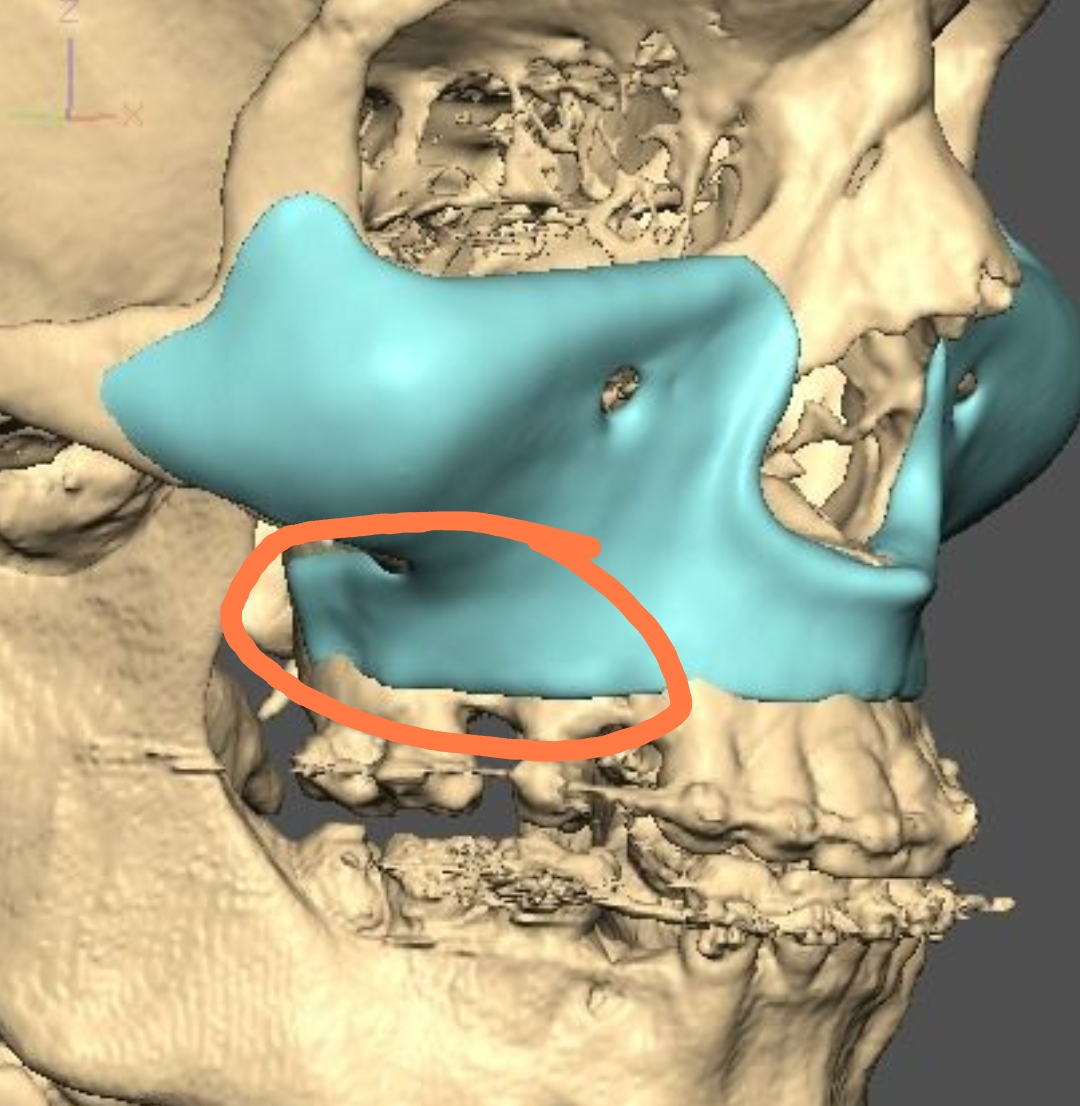

A lot changed since the initial design

current

It's going to be split into either 5 or 7 pieces.

current

It's going to be split into either 5 or 7 pieces.